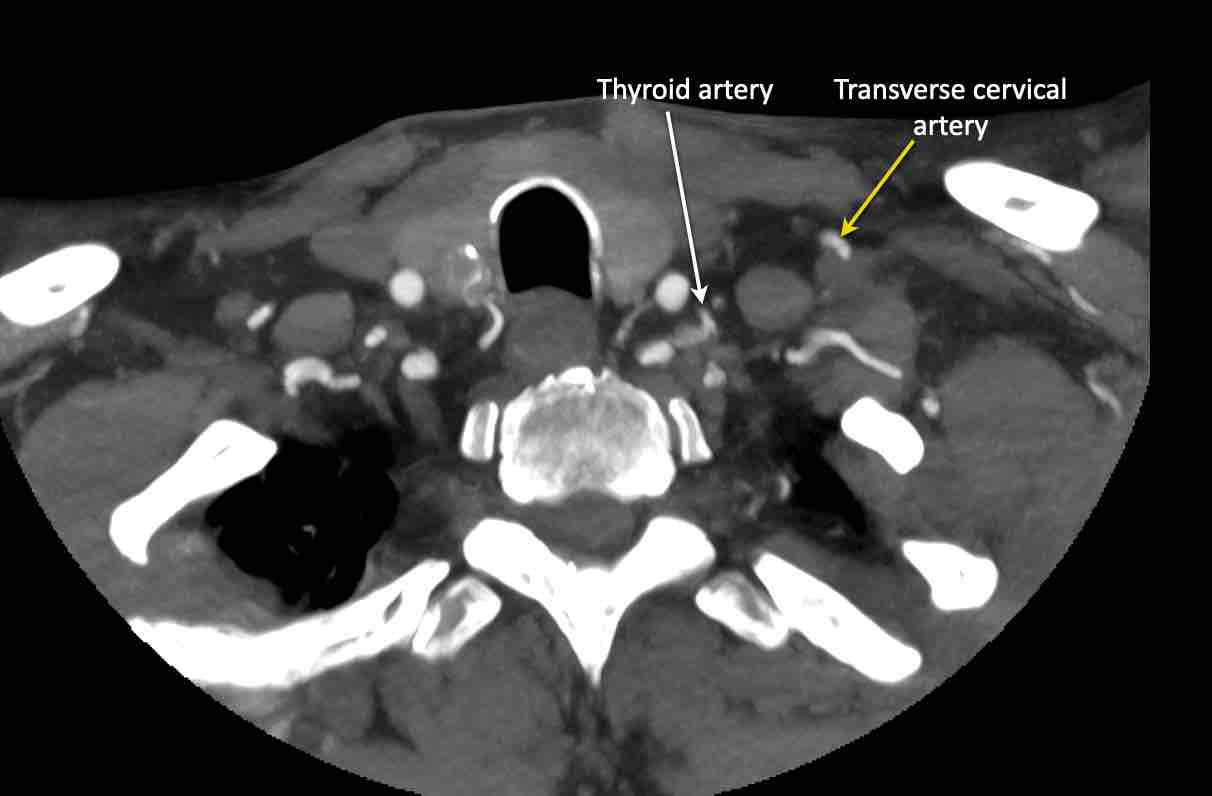

Động mạch cổ ngang

Cuộn qua các hình ảnh để xem giải phẫu của động mạch cổ ngang.